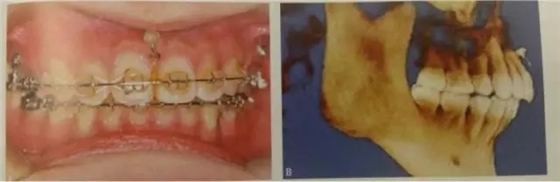

這是臨床上最常見的應(yīng)用方式,多用于需要強(qiáng)支抗內(nèi)收前牙,常種植于第二前磨牙與第一磨牙、第一磨牙與第二磨牙之間,應(yīng)根據(jù)X線片觀察牙根間距離和鄰近解剖結(jié)構(gòu)確定具體部位,采用微種植體一方面可以獲得絕對支抗以盡可能內(nèi)收前牙,另一方面可整體內(nèi)收6個(gè)前牙而不擔(dān)心支抗問題,節(jié)省了治療時(shí)間。

伴有露齦笑的深覆合常常需要壓低上前牙,而采用J鉤壓低前牙有時(shí)會因患者的不配合而無效,多用途弓等改善露齦笑的效果欠佳,因此微種植釘在壓低上前牙方面具有一定優(yōu)勢。常選用的植入部位包括前鼻棘下方、側(cè)切牙和尖牙根尖之間等。

“壓低后牙

頰側(cè)可以植于第二前磨牙和第一磨牙牙根間,第一磨牙頰側(cè)近遠(yuǎn)中根、或第一磨牙和第二磨牙根尖之間。對于有些上頜合平面偏斜、單側(cè)后牙鎖結(jié)、個(gè)別后牙因?qū)涎廊笔Ф扉L等患者,可以考慮單側(cè)后牙區(qū)植入微種植體。對于前牙開合畸形,下頜缺乏縱合曲線,spee曲線過于平坦,雙側(cè)后牙正鎖合等情況。

此外微種植釘支抗還可輔助阻生牙、埋伏牙、易位牙的牽引治療,對鎖合的矯治,調(diào)整合平面不平所致下頜偏斜,集合間隙修復(fù)豎直后牙均有較好的利用和發(fā)揮。